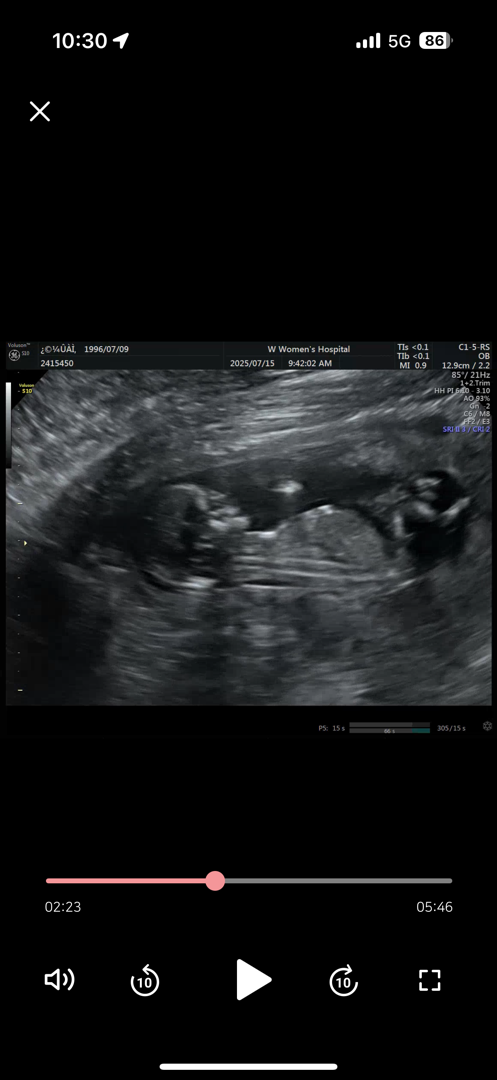

13주차 둥이 첫째예요! 각도법문의!

첫째아가예요!! ㅎㅎㅎ 각도법 봐주심 감사합니다 재미로 볼게용🩷

아들같아요